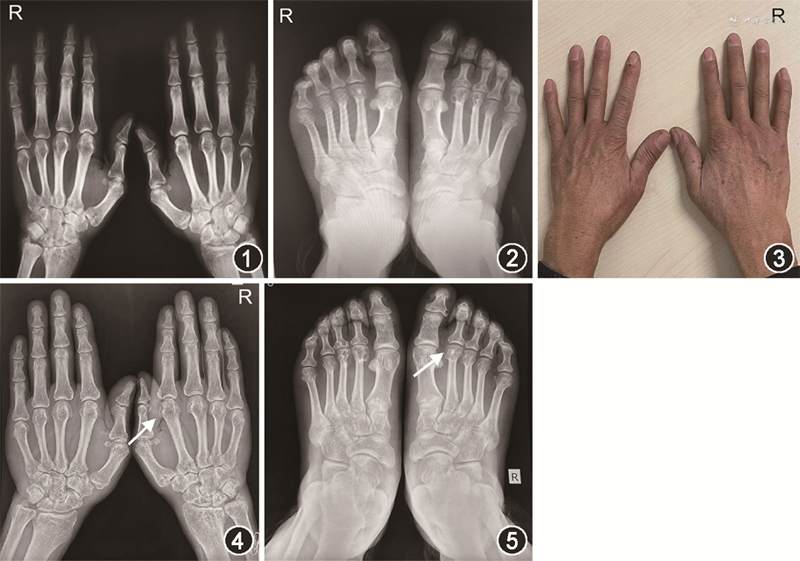

患者于2012年自行停用来氟米特,2015年3月症状再发,伴背、颈、肩疼痛,服用白芍总苷胶囊治疗,症状略有减轻,仍肿痛。于2015年7月来我院门诊就诊。查体:体重指数 24.22 kg/m2,一般情况可,浅表淋巴结未触及肿大,全身皮肤未见皮疹,未触及类风湿结节。结膜无充血,双肺呼吸音清,未闻及干湿性啰音,心脏各瓣膜听诊区未闻及杂音,腹软,肝脾未触及。颈部活动可,双上肢可抬举过肩,右肘不能完全伸直,无肿胀。双腕活动受限,稍肿。双手MCP1肿胀及压痛,右手PIP4及左手PIP4~5梭形肿胀,左足MTP2~4肿胀及压痛。双膝关节无肿胀。髋关节活动可,4字试验阴性。四肢肌力5级。辅助检查:白细胞计数 5.71×109/L,血红蛋白131 g/L,血小板计数 372×109/L;肝肾功能、血尿酸、肌酸激酶正常;红细胞沉降率(ESR)44 mm/1 h;抗CCP抗体:214 U/ml;抗核抗体谱(-)。双手X线:双腕骨间隙轻度狭窄,右侧腕关节面下可见骨侵蚀,双PIP关节间隙轻度狭窄,双侧PIP关节面下囊性变、轻度骨侵蚀(图1)。双足X线:双侧MTP1关节间隙狭窄,左侧MTP2~5关节面下囊性变、轻度骨侵蚀,穿凿样骨破坏,可见钙质沉积(图2)。

因新型冠状病毒肺炎疫情原因,近1年未随诊,2020年12月因间断双手MCP、PIP发作性肿痛就诊,发作前未干活,间断口服非甾体抗炎药,自觉较前止痛效果差,发作持续时间延长,再次就诊。查体双腕关节活动可,右MCP2~4、PIP2~4肿胀(图3),皮温高。ESR、血尿酸正常,hs-CRP 8.34 mg/L,双手X线示右腕、双手PIP关节间隙轻度狭窄,关节面下可见骨质侵蚀,右手MCP2~3近心端穿凿样骨破坏及钙质沉积明显(图4)。双足X线示双侧MTP1关节间隙狭窄,左侧MTP2~5关节面下囊性变、轻度骨侵蚀,可见穿凿样骨破坏、钙质沉积进展(图5),考虑类风湿关节炎稳定,可继续甲氨蝶呤的用量,结合病程、工作性质、典型发作性关节症状、典型影像学表现,考虑假性痛风可能,加用秋水仙碱 0.5 mg/次、1次/d,如1~2个月症状明显改善,可改为1次/隔日,若病情平稳建议半年复诊。